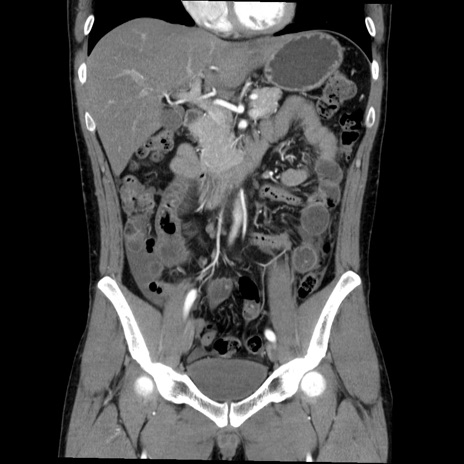

症例36(冠状断像)

【症例】20歳代 男性

【主訴】心窩部痛

【現病歴】今朝より上腹部痛あり。一旦軽快していたが再度出現したため救急要請。昨日夕に白身の魚を含む刺身を食べた。

【身体所見】BP 136/89mmHg、HR 74/min、BT 37.0℃、腹部:膨満、軟、心窩部に圧痛あり。反跳痛なし、筋性防御なし、腸雑音やや亢進あり。

【データ】WBC 17700、CRP 0.48